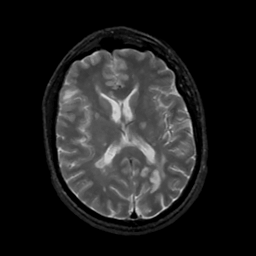

MR Study #5, March 10, 1991 -- Slice #30